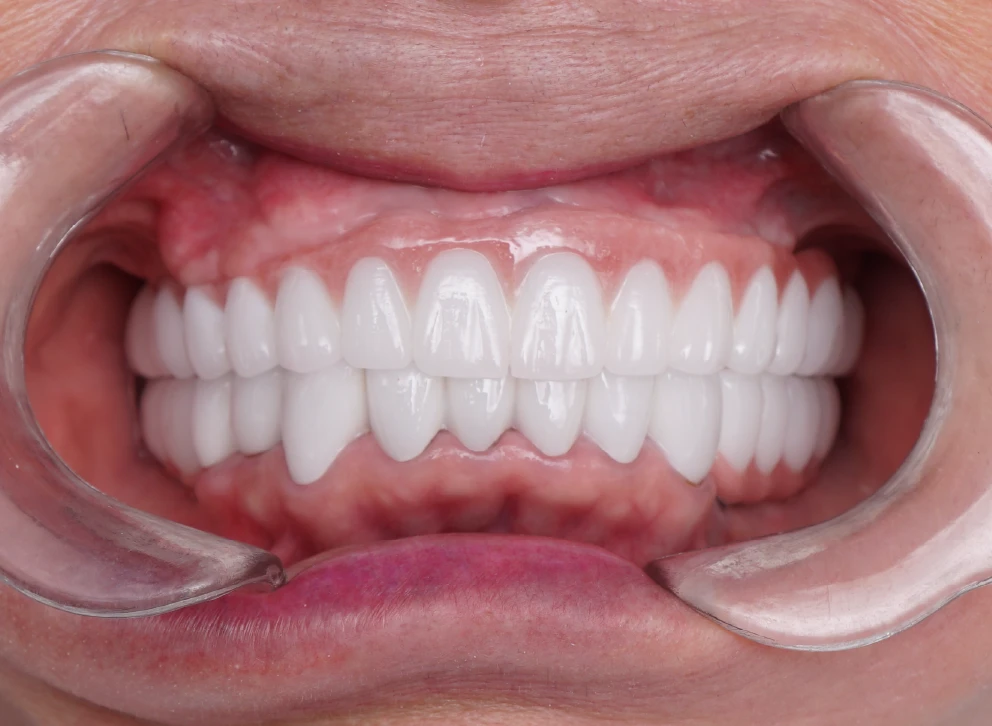

• Tình trạng răng trước đây:Mất răng toàn hàm trên và hàm dưới nhiều răng lung lay.

• Bác sĩ chỉ định:Cấy ghép 2 hàm Implant All On 6.

• Implant sử dụng:Implant Mis C1 Đức.

• Răng sứ sử dụng:Răng toàn sứ Zirconia Đức.

• Cấy ghép 2 hàm Implant All On 6

• Phục hình răng sứ trên Implant

Không phụ lại mong đợi của cô Biểu, đội ngũ I-DENT đã có thể giúp cô phục hình lại được hàm răng mới chắc chắn. Để có thể thỏa thích ăn nhai những món ăn yêu thích và lúc nào cũng tự tin, vui khỏe cùng người thân, bạn bè.